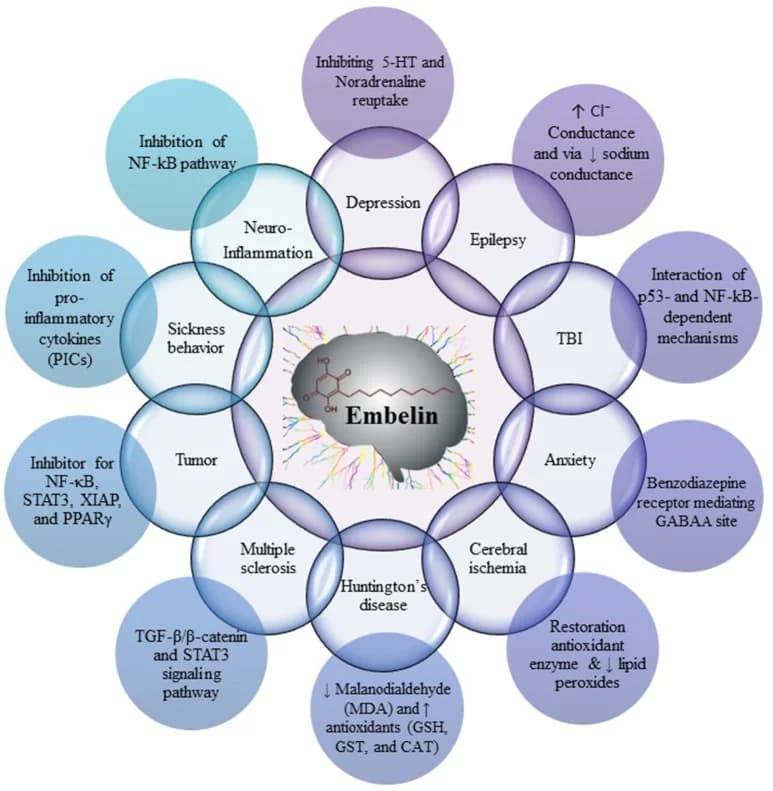

- Embelin R